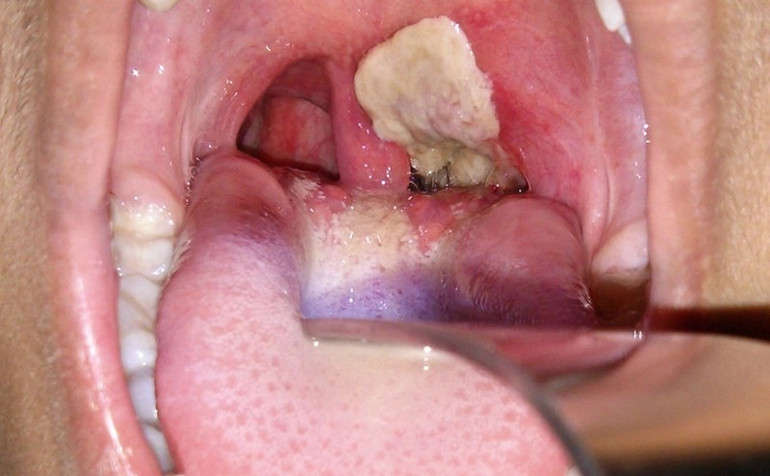

| Một trong những triệu chứng của bệnh bạch hầu là xuất hiện giả mạc tại vùng hầu họng. (Ảnh minh họa) |